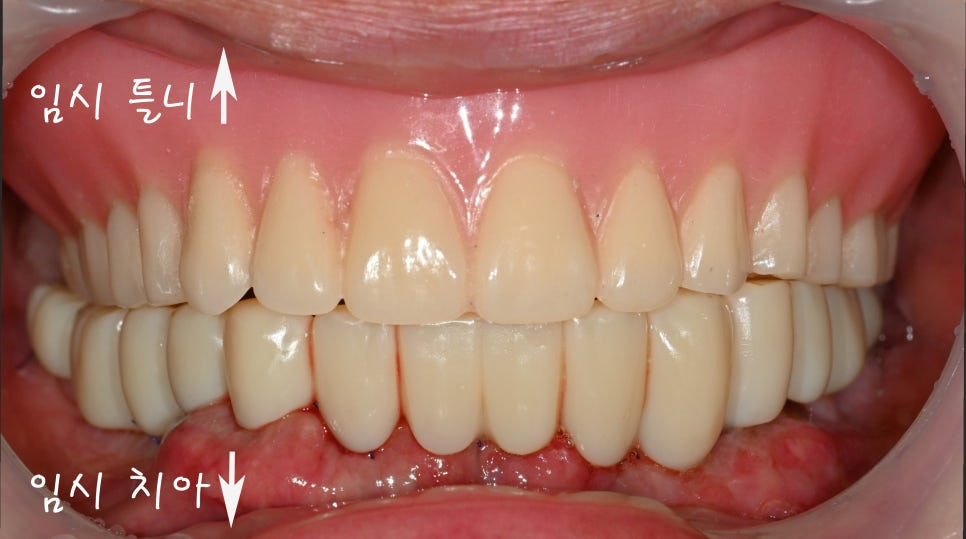

상악은 기성 어버트먼트를

장착하였으며

하악은 임시 치아를

제작하여 체결했습니다.

이렇게 위아래 다른 이유는,

2024.09.20

윗쪽는 전체 틀니를 사용해도

불편감이 크지 않은 반면

그에 반하여 아래는

의치가 오히려 더 힘들 수 있어

임시 보철을 체결한 것 입니다.

상악은 골 흡수가 많아

안정적으로 유착되려먼

하중을 부여하지 않는 것이

더욱 유리합니다.

그러므로 틀니가 더욱 적합했죠.

반대로 하악은 즉시 하중을

부하하더라도

치유 과정에 영향이 없어

임시로 치아를 올릴 수 있었습니다.